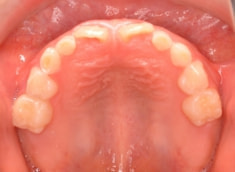

治療前

小児期ケース:反対咬合(受け口)

歯牙の大きさ(マテリアル)分析:偏差値55.2なので、歯のサイズは平均よりは大きめです